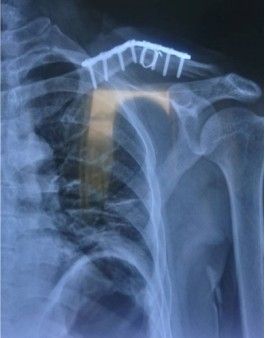

Большинство переломов могут быть диагностированы с помощью простых антеропостериальных рентгенограмм. Рентгенограммы наклона головки 20 ° устраняют влияние перекрывающихся грудных полостей. Пациенты должны быть рентгенограмма в положении самоподдерживания, чтобы лучше визуализировать смещение переломов. Веса для рентгенограммы помогает в оценке целостности ростральной клавикулярной связки в дистальной ключице или акромиоклавикулярной повреждениях суставов. Взятие рентгенограммы грудной клетки помогает исключить связанную торакальную травму, а укорочение может быть оценено путем сравнения с контралатеральной ключицей, а также исключая лопатологическую стенку.

3.5 Систематические сжатые пластины, реконструкционные пластины или пластиковые LCP могут использоваться для закрепления переломов ключицы. Пластины плавно расположены над или передней к ключице. Пластины более сильнее в биомеханических травмах, когда они расположены превосходно, особенно если внизу есть разбитый перелом, и их проще в визуализации. Необходима бикортикальная фиксация винтов, и отверстия должны быть просверлены с большой осторожностью, так как внизу риск повреждения нервов и кровеносных сосудов. Преимущества: безопасное бурение переднего винтового канала, приложение пластины, легкая контур.

Интраоперационное размещение системы LCP 3.5 перед ключицей, предпочтительно спереди ниже ключицы, позволяет ссылаться на здоровую ключицу, облегчая формирование пластины заранее и получает более длинную апертуру винта.

Выбор имплантатов пластин зависит от размера бокового костяного блока. Для бокового костяного блока требуется минимум 3 бикортикальных винта. В идеале, винты натяжения должны использоваться для наклонных переломов. Если костный блок слишком мал для фиксации, может использоваться крючка ключица.